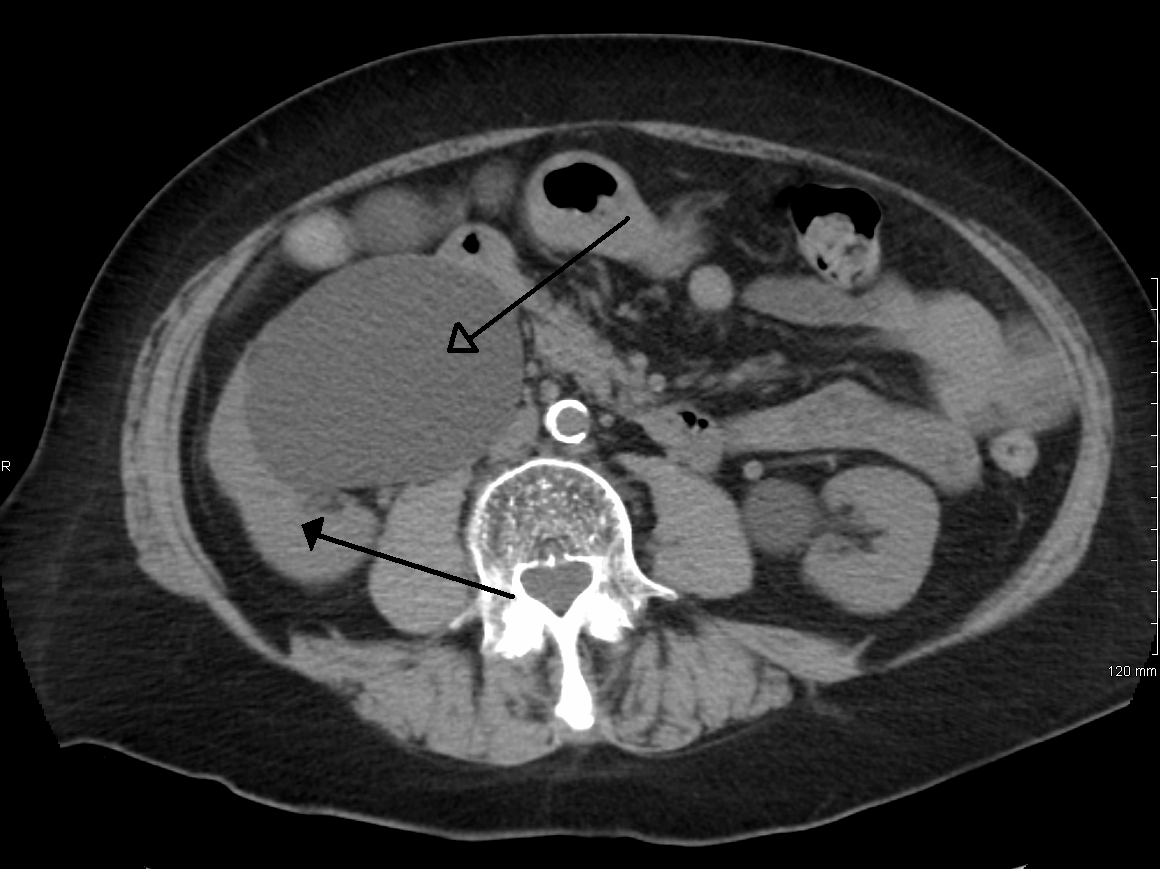

질병을 진단하려면 환자의 병력과 기타 신체 검사 정보를 알아야 한다. 이는 일부 영상 검사를 동반해야 한다. 일반적으로 초음파 검사를 사용하여 환자의 요로, 콩팥 등의 상태를 확인할 수 있다. 또한 CT 스캔과 MRI는 요로 및 폐쇄를 보다 명확하게 보여줄 수 있다.[8]

정맥 신우 조영술(IVU), 신장 초음파 검사, CT, MRI 등의 영상 검사도 중요하다. 초음파 검사는 요관과 신장을 시각화하고 수신증 및 수뇨관증 유무를 확인하는 데 유용하며, IVU는 막힘의 해부학적 위치 평가에 유용하다. 순행 또는 역행 신우 조영술은 IVU와 유사한 소견을 보이면서 치료 옵션도 제공한다. 실시간 초음파와 도플러 초음파 검사는 혈관 저항 검사와 함께 폐색이 요로 기능에 미치는 영향을 파악하는 데 도움이 된다.[12]

신 산통(소변에 혈흔이 섞인 옆구리 통증)의 초기 검사는 나선형 또는 헬리컬 CT 스캔이다. 이는 소변 흐름 폐색 여부와 다른 신장 기능도 보여준다. CT는 대부분의 결석을 확인할 수 있어 초기 검사로 흔히 선택되지만, 임신과 같이 방사선 노출을 피해야 하는 경우에는 사용하지 않는다.[13][14] 우연히 발견된 산전 수신증의 경우, 첫 검사는 산후 신장 초음파 검사다. 산전 수신증의 많은 사례가 자연적으로 해결되기 때문이다. 출생 후 며칠 이내에 시행하지만, 너무 이른 검사는 경미한 수신증을 놓칠 수 있어 4~6주 후 추적 초음파 검사를 권장하기도 한다.[15] 배뇨 방광 요도 조영술(VCUG)은 방광 요관 역류나 후부 요도 판막 같은 해부학적 이상을 배제하기 위해 시행된다. 수신증이 심각하고 요관 신우 접합부(UPJ) 또는 요관 방광 접합부(UVJ) 폐색이 의심되면, MAG-3 스캔과 같은 핵 영상 검사가 필요하다.[13]

- 4단계 (중증) – 3단계와 같지만 신장 실질이 얇아짐